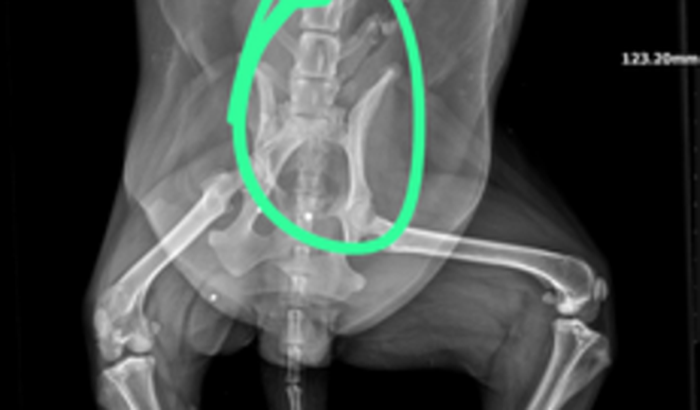

Oii, somos uma turma de amigos e veterinários que decidimos fazer essa vaquinha para pagar a cirurgia de pelve dessa cachorrinha, gostaria do apoio de vocês nessa causa muito importante para nós!  ver tudo

Oii, somos uma turma de amigos e veterinários que decidimos fazer essa vaquinha para pagar a cirurgia de pelve dessa cachorrinha, gostaria do apoio de vocês nessa causa muito importante para nós!